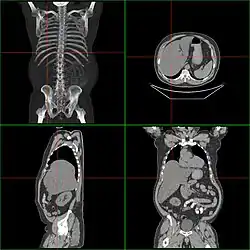

Гепатомегали́я — патологическое увеличение размеров печени.

Особенно выраженная гепатомегалия наблюдается при лейкозах и других гемобластозах, в результате массивной инфильтрации ткани печени злокачественными лейкозными или лимфобластными клетками, или в результате образования в печени очагов внекостномозгового (экстрамедуллярного) кроветворения. В этих случаях печень порой достигает огромных размеров, занимая более половины брюшной полости и иногда достигая веса порядка 10—20 кг.

Если размер печени по l. medioclavicularis dextra превышает 12 см или пальпируется левая доля в эпигастральной области, говорят об увеличении печени. Важно исключить опущение печени (например, при хронической обструктивной болезни лёгких или вздутии правого лёгкого) или расположение в правом верхнем квадранте других тканей (увеличенный желчный пузырь, опухоль почки или кишки). Размеры печени лучше определить посредством КТ или УЗИ. Важно оценить контуры и рисунок ткани органа; Увеличение тех или иных участков ткани; «каменистая» консистенция предполагает наличие опухоли; боль при пальпации говорит о воспалении (гепатит) или быстром увеличении размеров органа (недостаточность правого сердца, синдром Бадда — Киари, жировая инфильтрация).